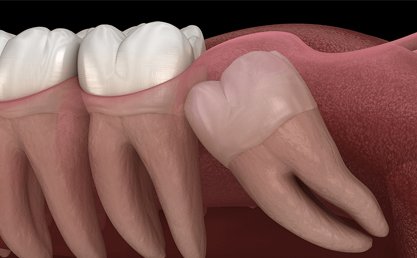

Wisdom Tooth extraction a surgical procedure to remove one or more wisdom teeth , located at the back corners of your mouth on the top and bottom.

• If a wisdom tooth doesn’t have room to grow, results in pain, food entrapment, infection or gum disease, tooth decay infection or other dental problems, you’ll likely need to have it pulled.

• Damaging the nearby tooth and while straightening other teeth (orthodontic treatment).